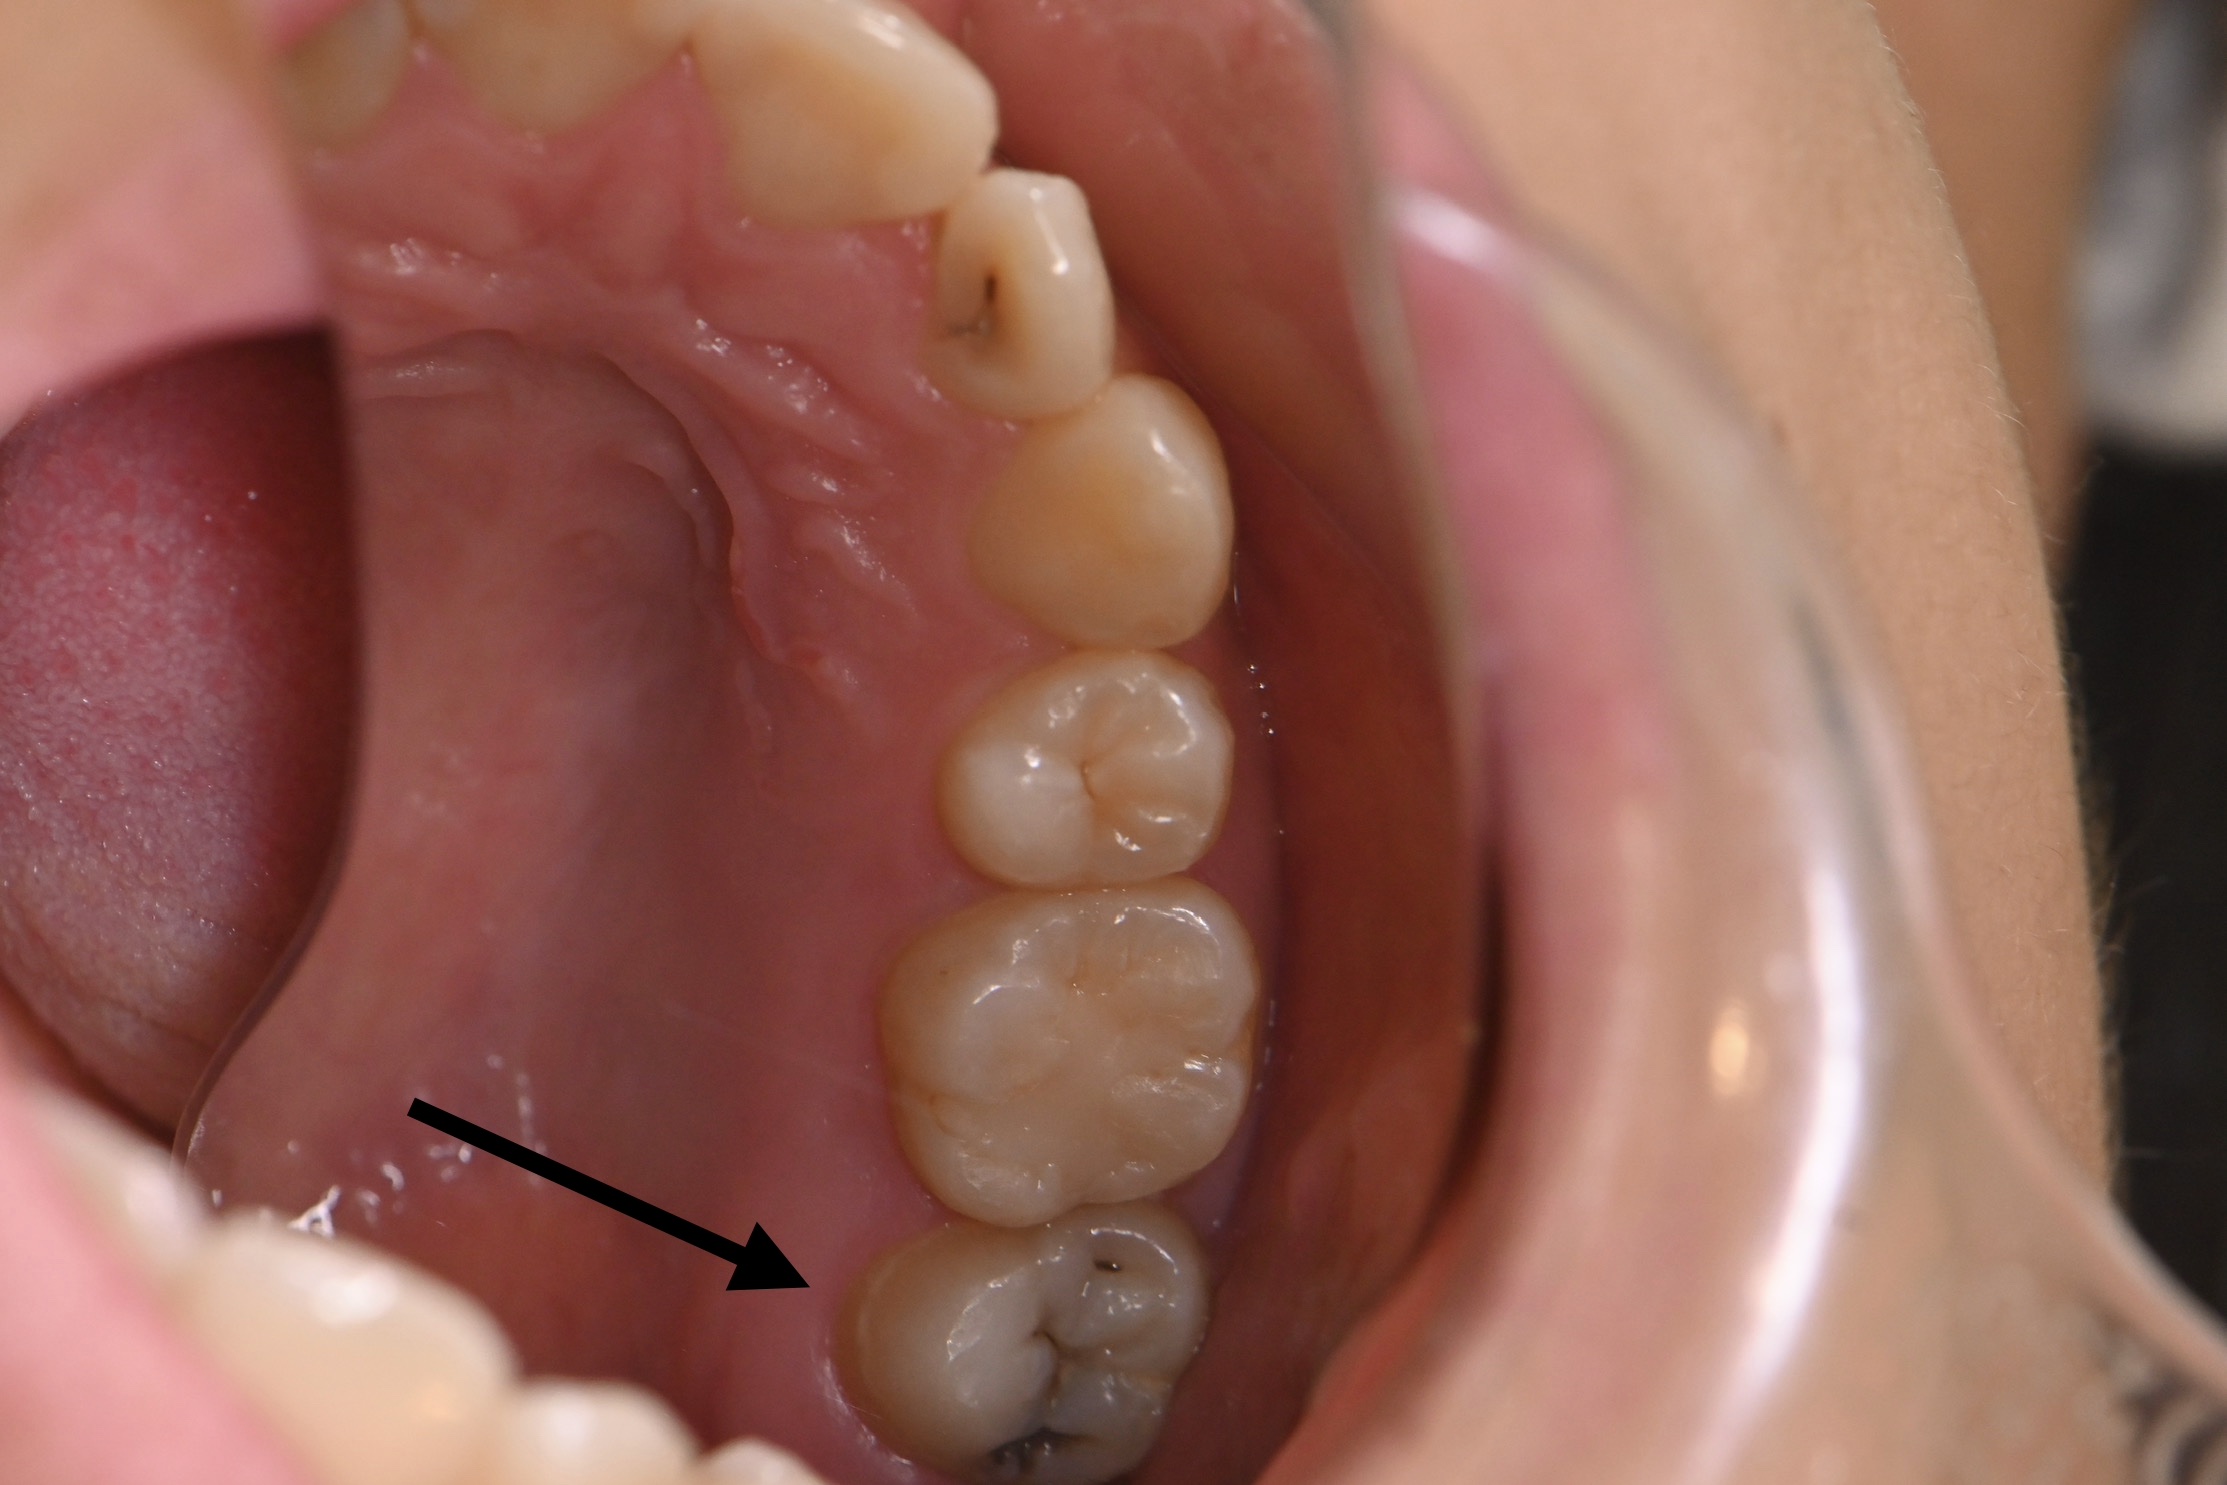

神経保護処置🦷

今回は右上7、MTAセメントの紹介になります。

痛みがなく、症状もなく、大きく虫歯になっていました🦷

【処置前】